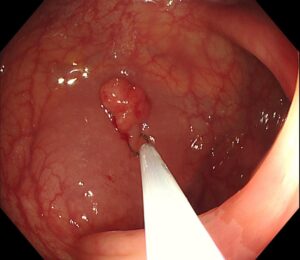

👉 局注針を内視鏡から出します(写真2)

(写真2)

👉 生理食塩水をポリープの下に注入し(写真3)、 粘膜下層がふっくらと盛り上がりました(写真4)

(写真3)

(写真4)